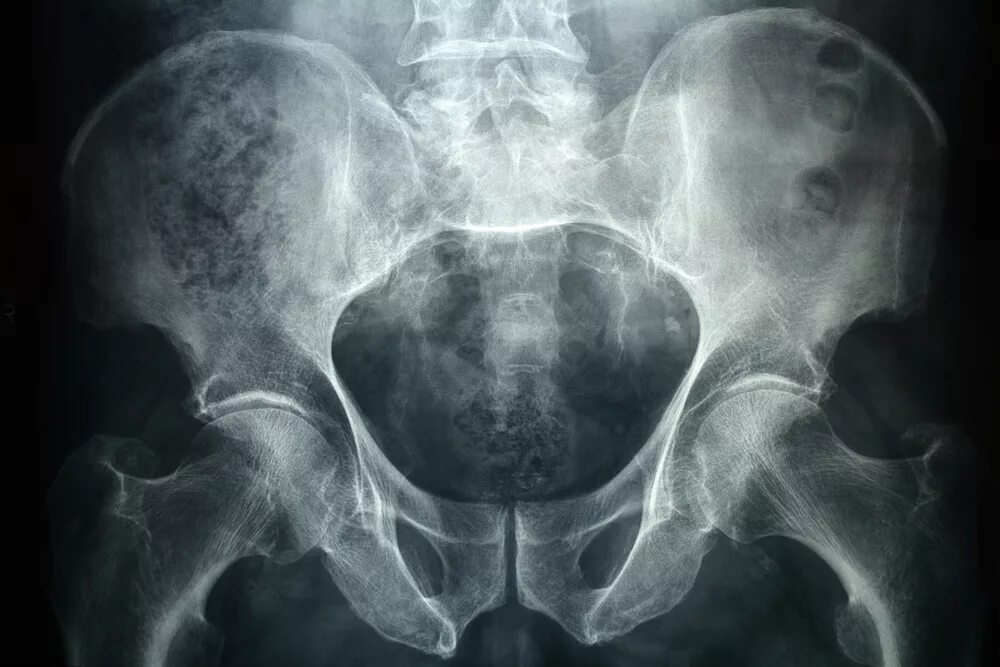

Снимок копчика